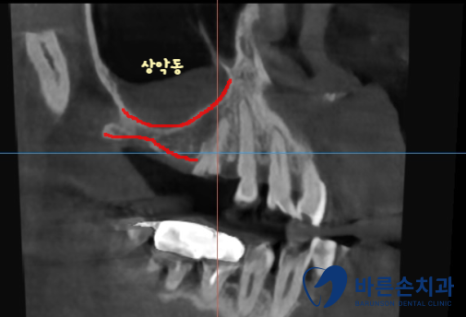

임플란트를 심기 위해서는 뼈가 충분히 있어야 하는데

상악동(빈 공간) 아래로 뼈가 너무 얇습니다.

상악동을 들어올려서 뼈이식을 충분히 하고 임플란트를 식립하기로 합니다.

이 수술 방법을 상악동 거상술이라고 해요.